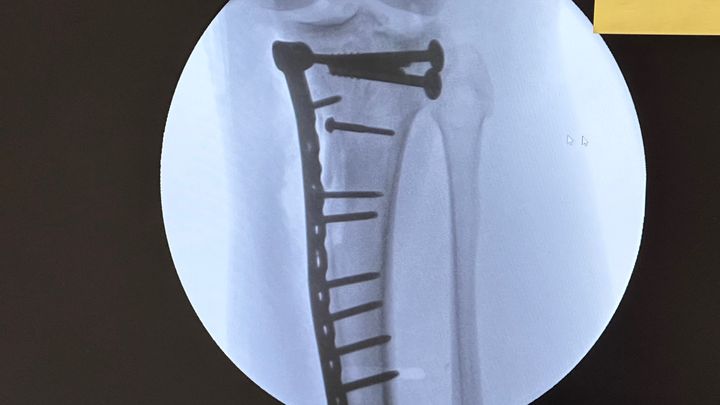

Hey all I was really not wanting to do this but I have come to a point where I really need helpI learned today that I will not be able to add weight to my leg for another 3 months♂️which is totally screwing me on work and with me not working bills are falling behind so if there is anyway way you can help me and my family out it would be greatly appreciated